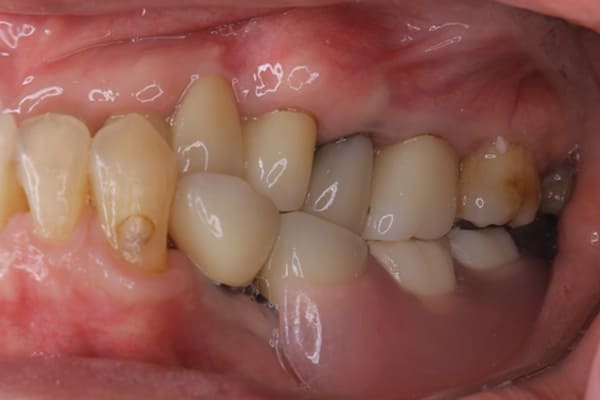

上あごに接する入れ歯に違和感がありになっていたとのことで、プラスチックが大きく削られた入れ歯をされていました。

そのため入れ歯の安定が悪く、お食事の際に入れ歯が動き、がたつきを感じられている状態でした。

前歯にバネにより見た目の問題も抱えておられました。

かみ合わせが低くなった歯を本来の高さに戻し、保険では使用できない歯に負担のかかりずらいバネで、歯の保存、審美性を確保しました。

前歯にバネを設定せず、見えない奥歯に維持力をもたせたバネを用い、またバネのかかる歯の負担軽減を目的に、被せ物は繋げることで強度を増す設計とすることで、入れ歯が動かずガタつき、審美性不良が解消されました。

部分入れ歯と対合歯

入れ歯を修理する中で、入れ歯の上あごの接触面積ではなく、厚みに対しての違和感と診断し、薄い金属を用いた従来の厚みを1/3程度にした入れ歯にすることにより違和感は消失しました。